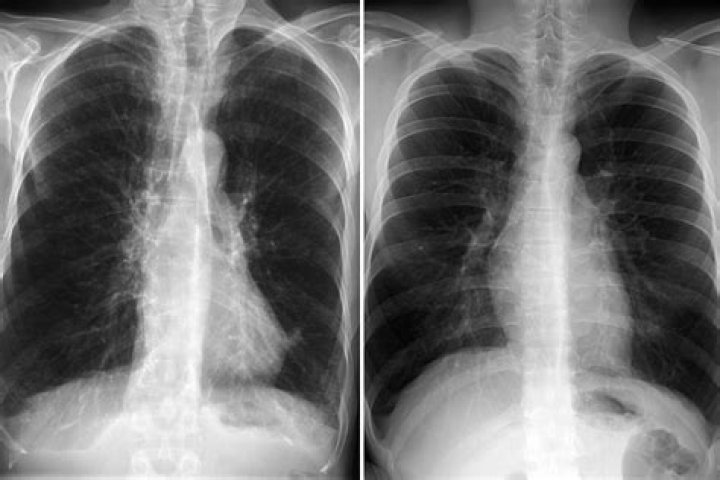

What can a CT scan detect in the lungs?

CT technology is used to detect pulmonary nodules, collections of abnormal tissue in the lungs that may be early manifestations of lung cancer. These nodules are often detectable by CT before physical symptoms of lung cancer develop.

Why would a doctor order a CT scan of the lungs?

CT scans of your chest can help your doctor diagnose, or rule out, various lung impairments. Some of these include blood clots, lung tumors or masses, excess fluid around the lungs (pleural effusion), emphysema, COPD, pneumonia, scarring of the lungs, tuberculosis or a pulmonary embolism.

Can a CT scan detect COPD?

CT images can identify emphysema better and at an earlier stage than a chest x-ray. They can also identify other changes of COPD such as enlarged arteries in the lungs. CT is sometimes used to measure the extent of emphysema within the lungs.

Will a CT scan show lung damage?

Although the CT scan cannot give a definitive diagnosis, it is helpful in the evaluation of lung diseases and conditions such as pneumonia, cancer, blood clots or damage caused by smoking.